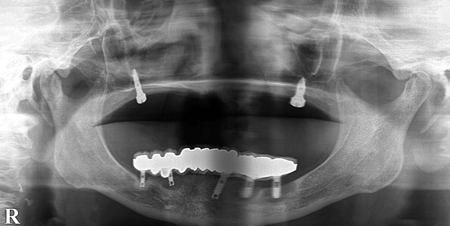

2024.12.1540代男性 天然歯をできる限り残すためにインプラントを用いながら虫歯の治療と噛み合わせを改善した症例